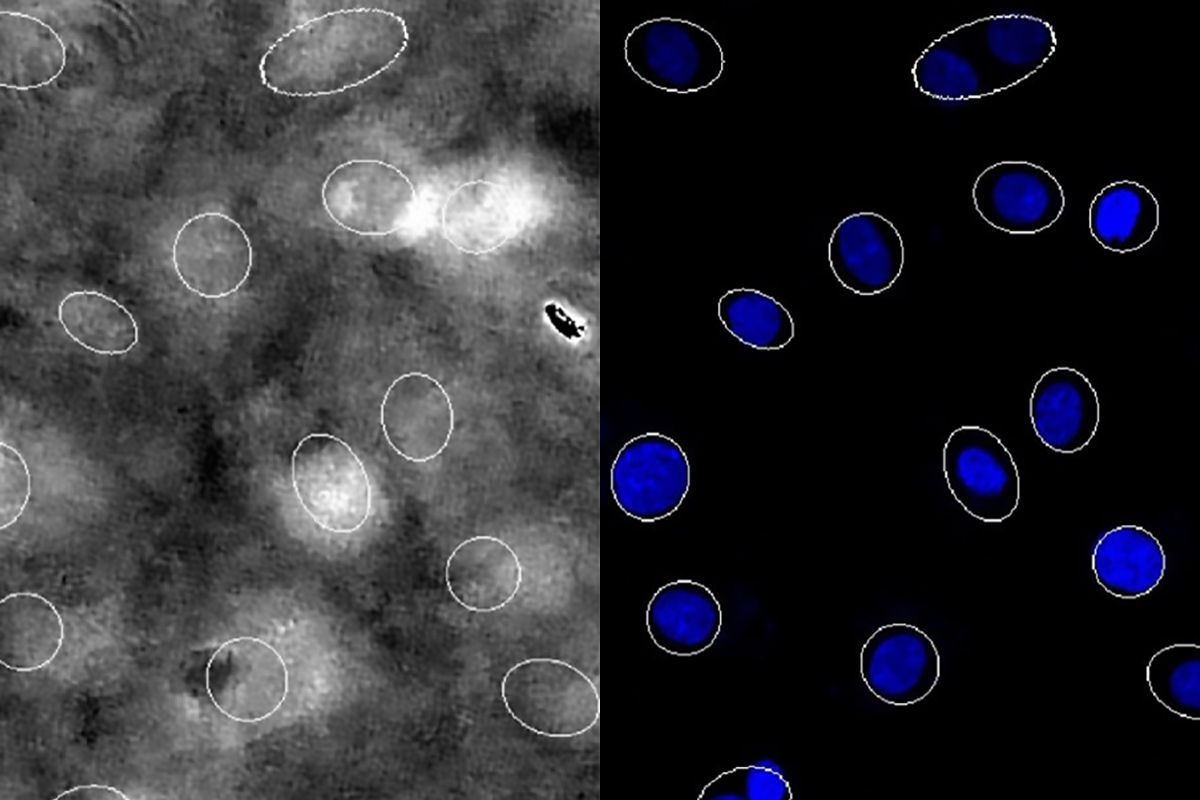

Small highlighted circles in grayscale indicate nuclei segmentation, next to bright blue circles in a similar location showing nuclei location after live-staining.

Precision robotics offers hope for heart disease treatment

The advanced drug testing system screens multiple potential therapies simultaneously in beating heart cells.